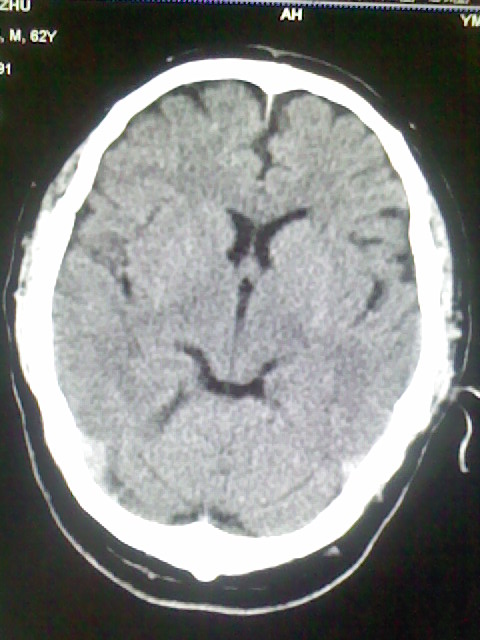

标题: CT15555:头痛 10余日 来诊大家帮忙看看 [打印本页]

标题: CT15555:头痛 10余日 来诊大家帮忙看看

脑萎缩

脑沟、裂增宽,提法脑萎缩,建议mt检查。

脑萎缩,以小脑为著。

脑沟、裂增宽,提示脑萎缩

老年脑

支持轻度脑萎缩。